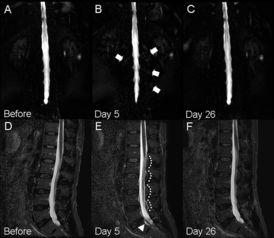

脊髓穿刺,听起来是不是有点吓人?其实,它是一种常见的医学检查方法,主要用于诊断脊髓病变、肿瘤、感染等疾病。通过视频,我们可以直观地看到手术的全过程,感受医生们的精湛技艺。

当一切准备就绪后,手术正式开始。医生会先在穿刺点处切开皮肤,然后用穿刺针穿过皮肤、肌肉层,直达脊髓。这一过程需要医生具备极高的精准度,因为一旦穿刺针偏离了方向,就可能造成严重的后果。

在手术过程中,医生会通过视频观察穿刺针的位置,确保其准确无误。同时,医生还会密切观察患者的反应,一旦发现异常情况,立即采取措施。